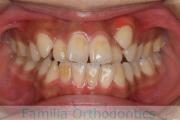

- ≫治療前

上顎

下顎

前歯の関係など

右側

正面

左側